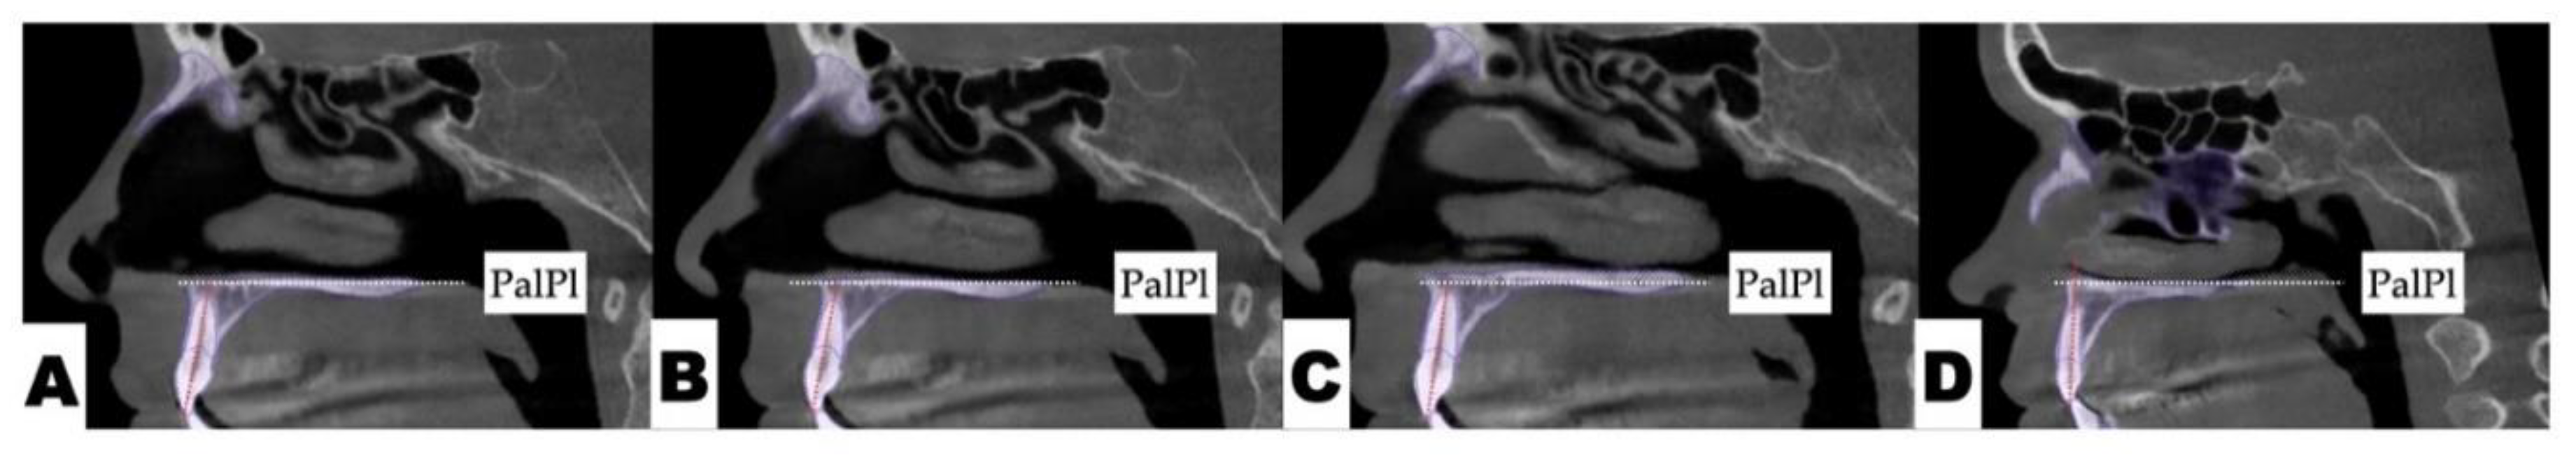

Post-expansion dentoalveolar movement progression is shown in Figure 13. The initial axial inclinations of maxillary incisors, microdontia with varying cross-sections of the maxillary incisor roots, and the pattern of disarticulation of the transverse suture all contributed to the degree of post-expansion incisor position asymmetry with perceived dominance of the buccal outline of the left maxillary segment compared to the right side. The dentoalveolar tooth positions, along with the differential initial root inclinations, were progressively corrected with directly printed aligner orthodontic movements (Thera-Hartz TA-28, Graphy, Seoul, Korea). Post-alignment axial inclinations of the maxillary incisors are shown in Figure 14.

Figure 14. The sagittal view of the axial cross-section of maxillary incisors after aligner axis correction: A—maxillary right lateral incisor; B—maxillary right central incisor; C—maxillary left central incisor; D—maxillary left lateral incisor. The axial inclination of all maxillary incisors has improved, with a significant reduction in buccal root torque of the maxillary left central and lateral incisors with directly printed aligner orthodontic movements.

Post-expansion dento-alveolar correction was performed using direct printed aligners (DPA). The efficacy of the DPA has been shown in multiple studies [19,20,21], which describe their higher accuracy, precision, efficacy, and shape-memory effects along with higher degree of root control due to thermoelasticity of the Thera-Hartz resin and appliance design incorporating longer margins. DPAs with shape-memory effects were used for post-expansion orthodontic treatment in both cases to facilitate and improve the quality of orthodontic tooth movements post-expansion. NemoCast (Nemotec, Madrid, Spain) planning software was used to plan orthodontic tooth movements and allow precise positioning of the roots by merging intraoral scans and CBCTs. Aligners were 3D printed using Graphy Thera-Harz TA-28 resin and compatible 3D printers.

Significant improvement in midline orientation, axial root inclination, space re-distribution was achieved over the course of 20 months post-expansion.